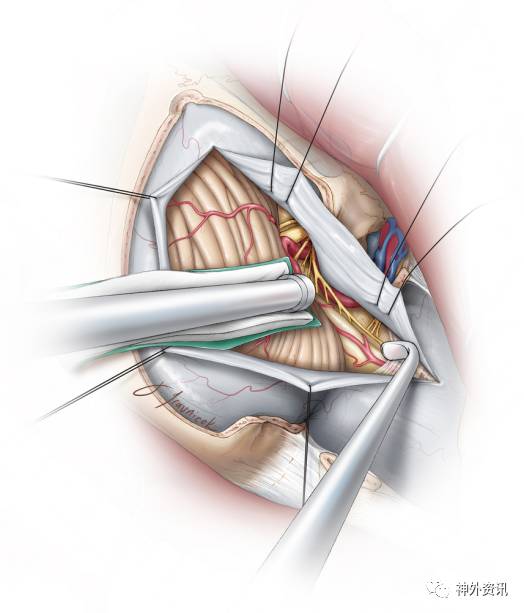

图4:远外侧入路的患者体位。

采用曲棍球切口,从C3水平至枕外隆突,然后水平向外侧延伸至乳突尖水平,之后切口再适当向下延伸。沿着白线需要留下筋膜瓣作为软组织,等缝合切口时使用。肌肉从骨和乳突分离,形成单一皮肌瓣向外下侧翻转。

枕骨大孔和寰椎后弓需要暴露出,这样可以上下扩大手术操作的空间。原则上来说,颅骨切除的范围:下至枕骨大孔,外侧至乙状窦和枕骨髁,横窦不需要暴露。

图5:右侧远外侧入路肌皮瓣的分离如上图所示。枕骨髁的磨除对于大部分PICA动脉瘤病例来说不是必要的。但是,骨瓣的去除在外侧必须到达枕骨髁水平(左下图)。骨质的去除范围和硬膜外椎动脉入硬膜内处向平齐(右下图)。

图6:呈曲线形剪开硬膜,将硬膜翻向外侧,内侧硬膜需要尽可能向内侧剪开,这样可以最大程度暴露外侧脑干。尽早的识别出椎动脉,打开覆盖在椎动脉表面的蛛网膜,放出脑脊液。手术过程如上图所示,需要注意的是术野外侧小脑的牵拉方向。